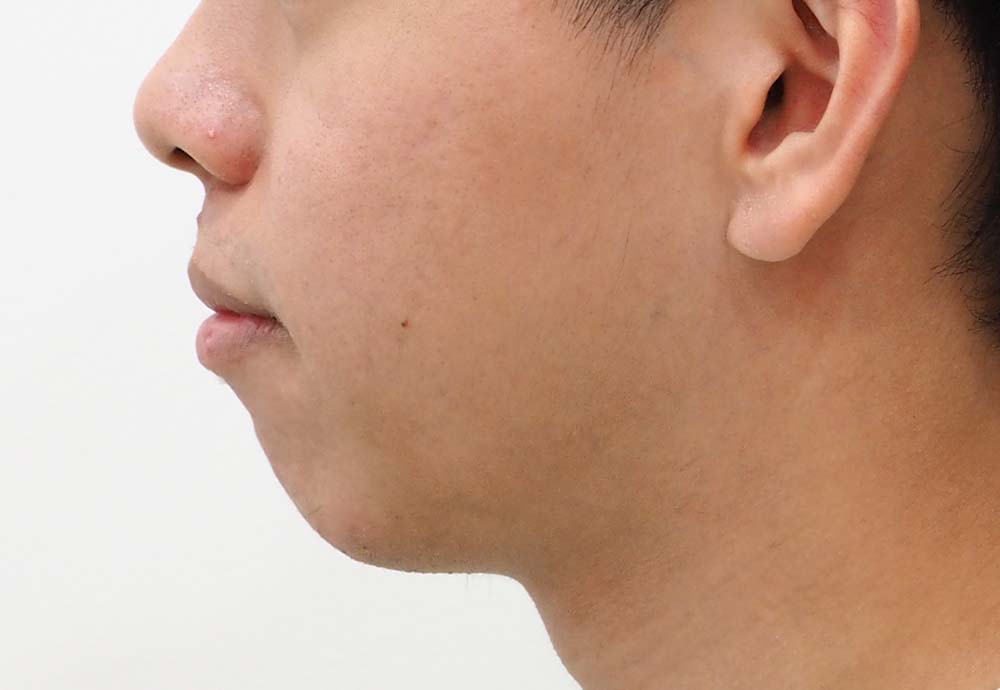

Dental Condition: Protruded side profile

In the right hands, braces can also subtly improve overall facial harmony and aesthetics (while correcting underlying jaw and tooth alignment issues).

Unlike metal braces that often rely on extraction to create space, clear aligners allow gentle arch expansion and digitally planned movement (distalization etc) to ensure the least compromise in facial profile.

Perfect if your facial profile makes you unsuitable for extraction.